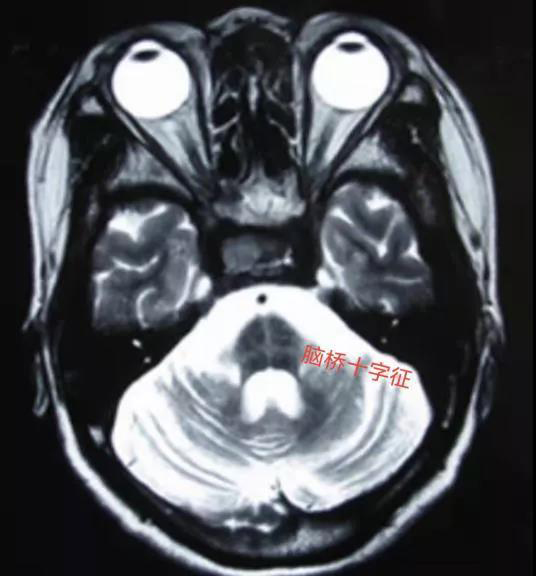

图 |核磁提示脑桥十字征